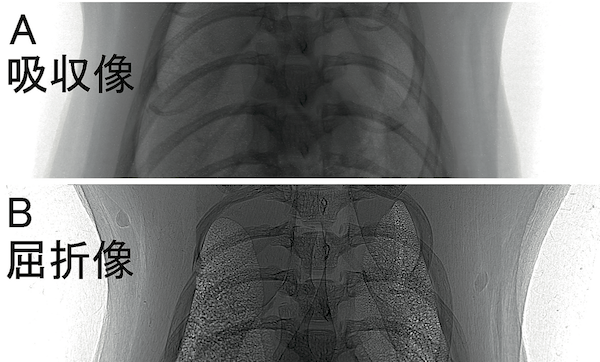

図3 ラットの肺の中の空気の様子。

図3 ラットの肺の中の空気の様子。屈折像では、中央に枝分かれした気管支が、左右には肺胞と呼ばれる直径0.1 mm位の小さな袋が重なって見えています。